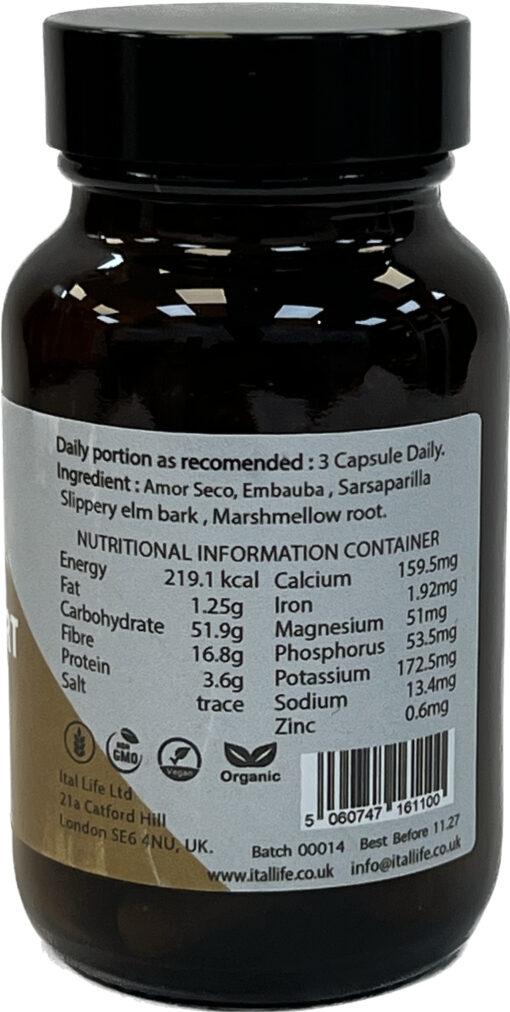

Ingredients: Amor Seco, Embauba, Sarsaparilla

Contains NO… yeast, wheat, gluten, salt, soy protein, milk/dairy, corn, sodium, sugar, artificial colouring, pesticides, preservatives, flavouring, or no animal or animal by-products.

Warning: If you are pregnant, nursing or taking any medication, or have any medical condition, please consult your healthcare practitioner before taking this product. Keep out of the reach of children. Store in a cool dry place.